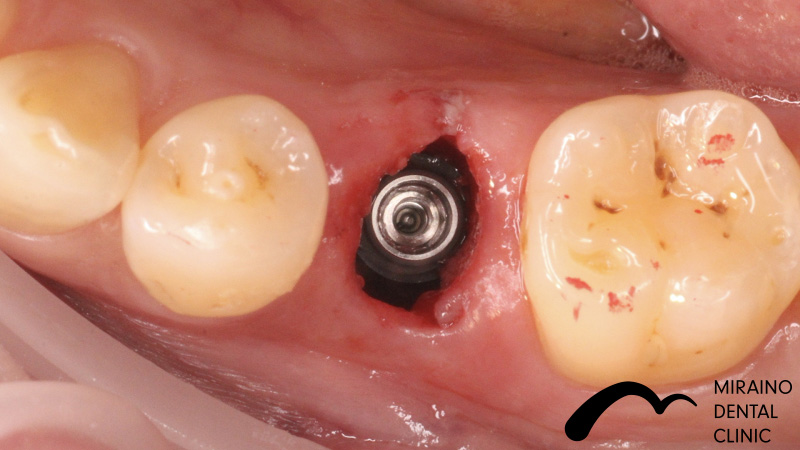

インプラントの症例

Case1

| 施術名 | インプラント |

| 施術の概要 | 10年前ほどに根の先に膿ができて抜歯。 前医では骨が少なくなってしまってインプラントは不可能ということで当院来院。 インプラントOPE時に仮歯まで作成し見た目の回復まで行いました。 その後OPE後3ヶ月で最終の被せ物装着する。 |

クリックして詳細を表示

| 施術の内容 | インプラントは、従来の入れ歯やブリッジとは違い、天然の歯と同じような強くて、美しい歯を取り戻す治療法です。 失った歯の代わりに人工の歯根を埋め込み、その上に人工の歯を装着。 健康な歯を削ることなく、新しい歯が蘇ります。 2~3か月後に上部構造(歯の部分)を装着してかみ合わせを回復させます。 |

Case2

| 施術名 | インプラント |

| 施術の概要 | 噛んだら痛い、を主訴に来院。 過去に神経の治療をして残していた歯が折れており保存不可能→抜歯適応と診断。 インプラントOPE時に、抜歯~仮歯まで作成し見た目の回復まで行った。 その後OPE後3ヶ月で最終の被せ物装着する。 |

クリックして詳細を表示

| 施術の内容 | インプラントは、従来の入れ歯やブリッジとは違い、天然の歯と同じような強くて、美しい歯を取り戻す治療法です。 失った歯の代わりに人工の歯根を埋め込み、その上に人工の歯を装着。 健康な歯を削ることなく、新しい歯が蘇ります。 2~3か月後に上部構造(歯の部分)を装着してかみ合わせを回復させます。 |